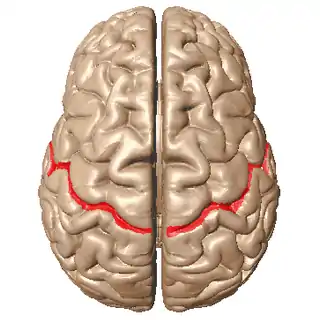

| Diagram showing the central sulcus of the brain. | |

Benign Rolandic epilepsy or self-limited epilepsy with centrotemporal spikes (formerly benign childhood epilepsy with centrotemporal spikes (BECTS)) is the most common epilepsy syndrome in childhood.[1][2] Most children will outgrow the syndrome (it starts around the age of 3–13 with a peak around 8–9 years and stops around age 14–18), hence the label benign.[3][4] The seizures, sometimes referred to as sylvian seizures, start around the central sulcus of the brain (also called the centrotemporal area, located around the Rolandic fissure, after Luigi Rolando).[5]